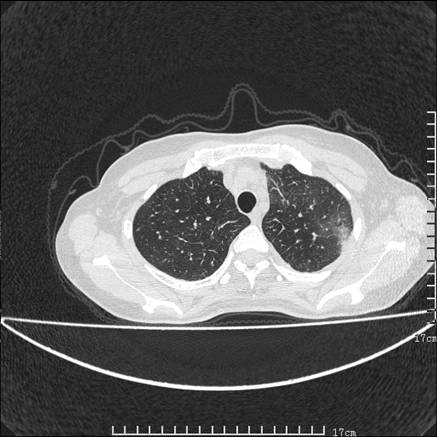

女,46岁,患胃溃疡多年,溃疡大小约1.0cm左右,后于5年前手术,病理为胃癌。主诉:半月前感冒后胸闷,气短,有咳嗽,无明显咳痰,无发热。偶有腰背部不适。

以下为高分辨扫描图像

双肺小叶间增厚,双肺散布粟米影和磨玻璃状影,以双肺上叶为重。结合病史考虑转移(癌性淋巴细管炎)可能性大。

结合病史:认为是典型肺部癌性淋巴管炎、淋巴结转移。请看图解。

正如caihe主任所言,影像表现结合临床病史应该支持肺癌性淋巴管炎;上肺大片边缘不清的渗出病变,多系感染所致,临床有感冒病史并咳嗽表现。肺癌性淋巴管炎临床一般无咳嗽、咳痰症状。